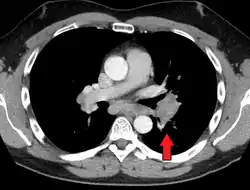

Hilar adenopathy especially on the person's left (AP CXR) -

Hilar adenopathy especially on the person's left (transverse CT)